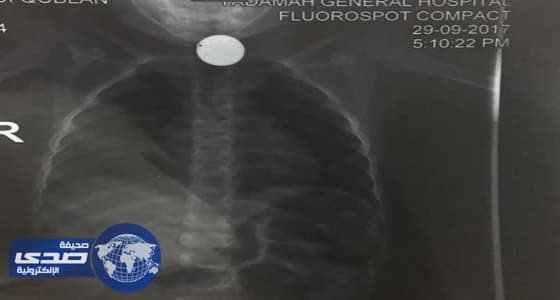

أستقبل قسم الطوارئ بمستشفى الولادة والأطفال بنجران طفل يبلغ من العمر 3 سنوات يعاني من صعوبة بالتنفس وكثرة اللعاب بسبب إبتلاع جسم غريب .

وعلى الفور تم إجراء الفحوصات اللازمة والتي أظهرت بالأشعة وجود جسم غريب بالمرئ وطبقا لمعايير حقوق المرضى تم شرح الحالة لوالد الطفل والخطة العلاجية لاستخراج الجسم الغريب مع أخذ موافقته على إجراء منظار عاجل .

ونجح الفريق الطبي في استخراج الجسم الغريب (قطعة معدنية) بحجم 2 سم،مما ساهم في استقرار حالة الطفل.